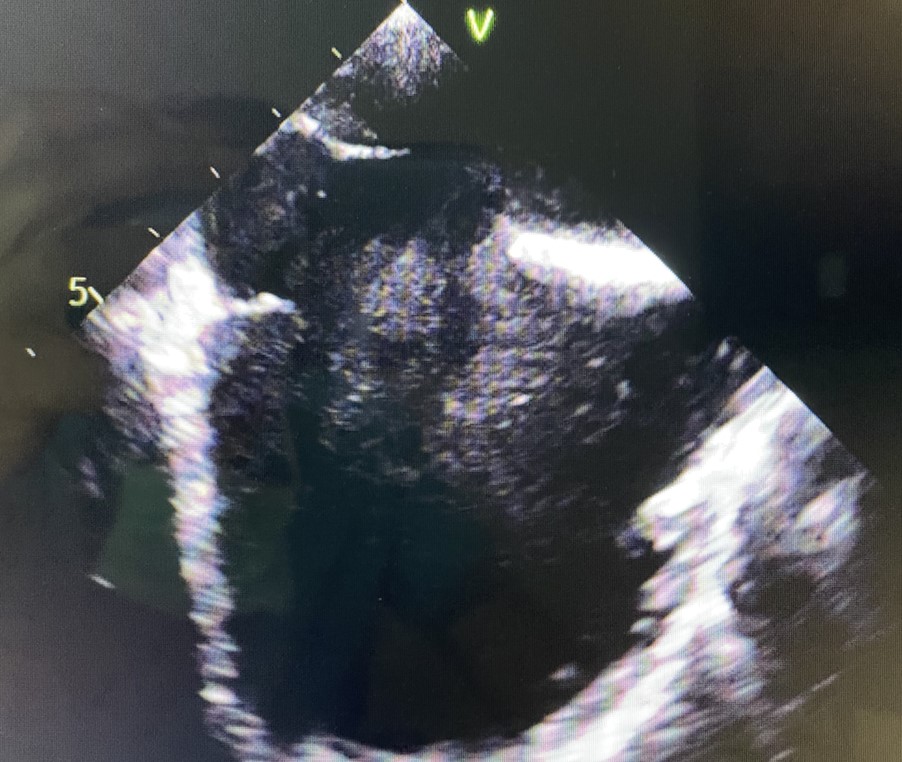

Transesophageal Echocardiogram showing large ASD

Both PFOs and ASDs can be detected through various imaging tests, such as echocardiograms. Treatment options for these conditions may vary depending on their size and whether they cause any symptoms or complications. Small PFOs and ASDs that don't cause problems may not require treatment. However, larger defects or those causing issues may be treated with procedures to close the hole, either through open-heart surgery or minimally invasive catheter-based techniques. Treatment decisions are made on an individual basis, and patients with these conditions require medical follow-up and monitoring to manage their heart health effectively.